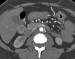

Filmsequenz zu Abbildung 1c: A.mesenterica inferior Die KM-verstärkte MDCT-Angiographie zeigte die kurzstreckige hochgradige Abgangsstenose der A. mes. sup. (Pfeil) und den Verschluss der A. mes. inf. (Pfeilspitze). |